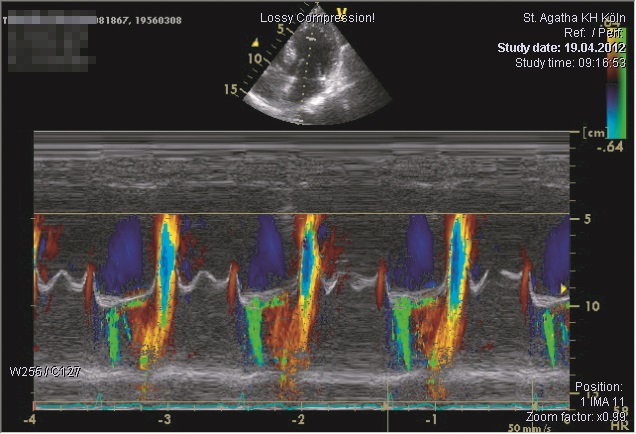

Mit der Echokardiographie kann die Herzaktion in Echtzeit dargestellt werden. Den Blutfluss beobachten man dabei unmittelbar mit der Farbdopplertechnik.

Damit wird die Funktion der Herzklappen wie auch der Herzmuskulatur beurteilt und erkannt, ob eine Herzoperation notwendig wird.